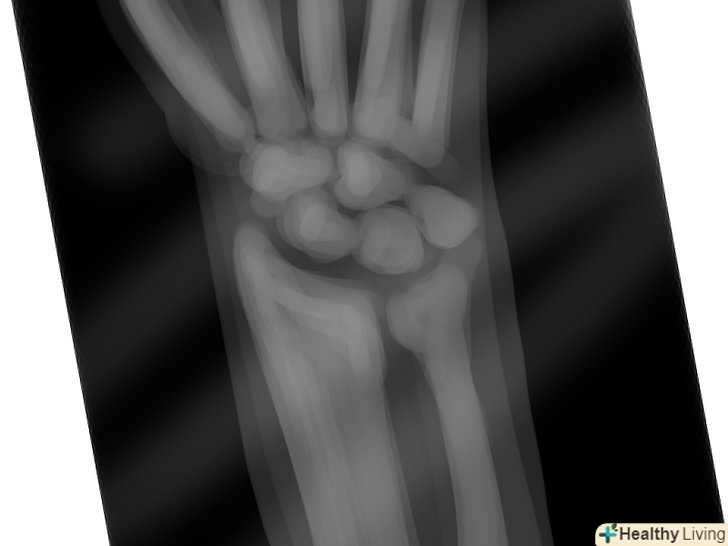

Відвідайте лікаря.у разі серйозної травми зап'ястя, яка супроводжується сильним болем, набряком, синцем і/або втратою рухливості долоні, слід негайно звернутися до сімейного лікаря або в пункт невідкладної медичної допомоги, щоб вам могли поставити точний діагноз. Розтягнення зап'ястя 3 ступеня супроводжується серйозним пошкодженням зв'язок, і для його лікування потрібне хірургічне втручання.[14] лікар також перевірить, чи немає у вас перелому або зміщення кісток, запального артриту (наприклад, ревматоїдного артриту або подагри), синдрому зап'ястного каналу, інфекції або гострого тендиніту.- Для постановки точного діагнозу лікар може призначити рентгенівське дослідження, сканування кісток або дослідження нервової провідності. Крім того, лікар може направити вас на аналіз крові для того, щоб виключити ймовірність ревматоїдного артриту або подагри.